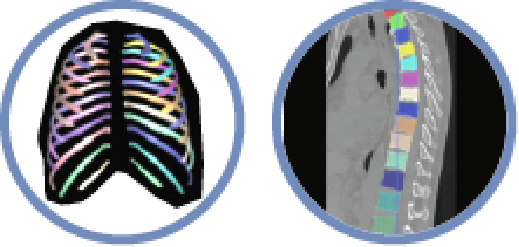

Precision in Musculoskeletal

▪ Rib Analysis

▪ Spine Analysis

Precision in Cardiology

▪ Coronary Analysis

▪ Coronary Calcification Analysis

▪ Cardiac Function Analysis

Precision in Pulmonary

▪ Nodule Analysis

▪ Emphysema Analysis

▪ Pneumonia Analysis

Precision in Oncology

▪ Liver Analysis

▪ Pelvic Masses